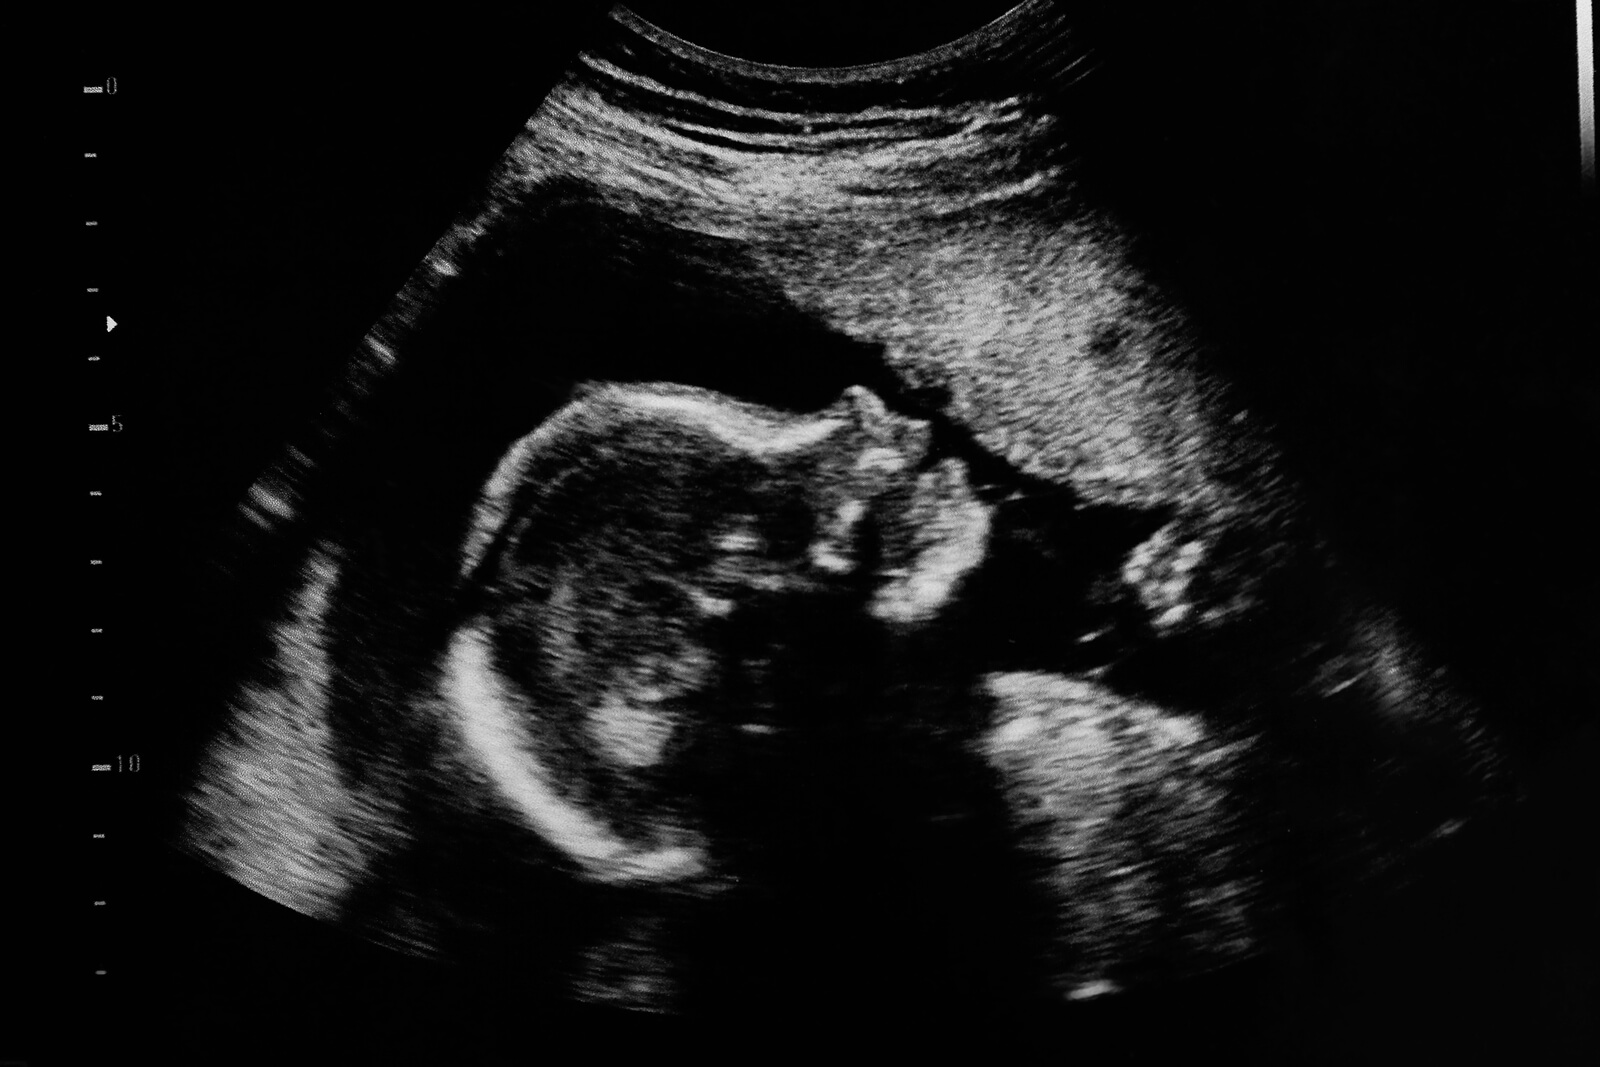

La pratique obstétricale actuelle est loin de celle d’il y a seulement 50 ans. Est-ce que la mise en place des échographies dans le cadre de la routine des contrôles de grossesse a marqué un avant et un après. Aujourd’hui, nous disposons d’appareils à ultrasons modernes et de professionnels bien formés pour évaluer en détail le développement du fœtus et diagnostiquer (ou traiter) les pathologies aux premiers stades de la grossesse.

Comme pour tout test complémentaire, l’échographie de grossesse nous donne des informations précieuses sur l’état de santé de la mère et du bébé. Mais cela ne veut pas dire qu’elle soit la seule forme d’évaluation, loin de là, infaillible. En ce sens, il est essentiel que ceux qui la pratiquent aient une formation suffisante pour interpréter chaque donnée et la contextualiser de manière appropriée.

L’échographie présente de nombreux avantages de par son aspect technique. En effet, elle ne nécessite pas de matériel trop sophistiqué, elle n’émet pas de rayonnement, elle peut être pratiquée tout au long de la grossesse et elle est sans danger pour le fœtus et sa mère.

Entre les semaines 19 et 21, il est judicieux d’effectuer la deuxième échographie, qui a pour objectif principal d’évaluer la formation de toutes les structures du bébé. Ce type d’examen est connu sous le nom d’échographie morphologique ou de scintigraphie fœtale.

Grâce à la disponibilité d’équipements d’imagerie à haute résolution, il est possible d’évaluer soigneusement les différents organes et systèmes du fœtus, de détecter les malformations précoces qui doivent être corrigées in utero ou peu de temps après la naissance.